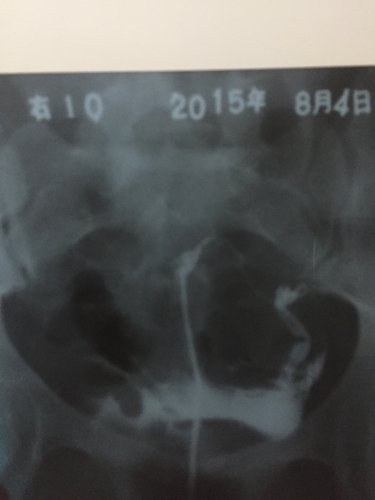

今天在哈尔滨玛丽亚妇产医院,我是因为附件炎疼痛去检查的。做了检查,左侧和右侧输卵管都堵了,右侧堵的比较严重,还有点炎症,做了好多项检查和治疗,我只做了左侧的通水术,右侧还没做,太夫说让我明天接着去通右侧的,和治疗消炎,可右侧的做起来要比左侧的难,不好通,我是想问?我不想在这家医院看了,我8号到我工作的城市做,会不会去医院再让我做一些检查呢?我在这里今天花了4千多了